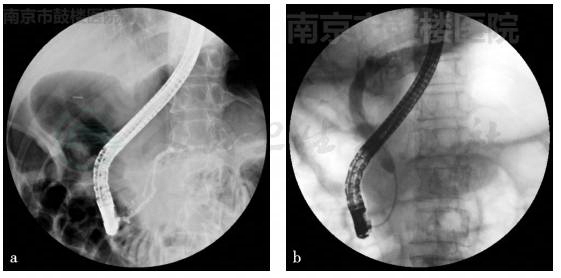

(3)ERCP

胆总管下段狭窄,狭窄段长约3cm,狭窄以上的胆总管及肝内胆管轻度扩张,胰管轻度扩张(图4)。

图4 ERCP结果

a. 胰管造影;b. 胆管造影